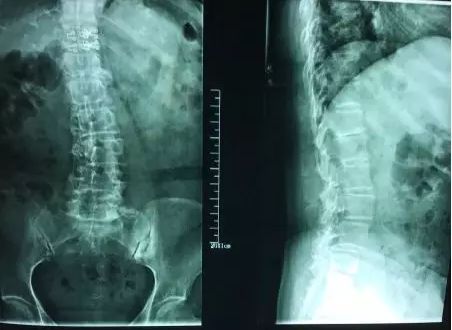

(本次就诊时的X光片)

我们看这张片子,脊柱的侧弯畸形、骨质增生、椎间盘突出、骨盆的旋移等病理改变都是很明显的。如果一名不熟悉的患者拿着这样一张片子来找你看,你知道从哪下手吗?